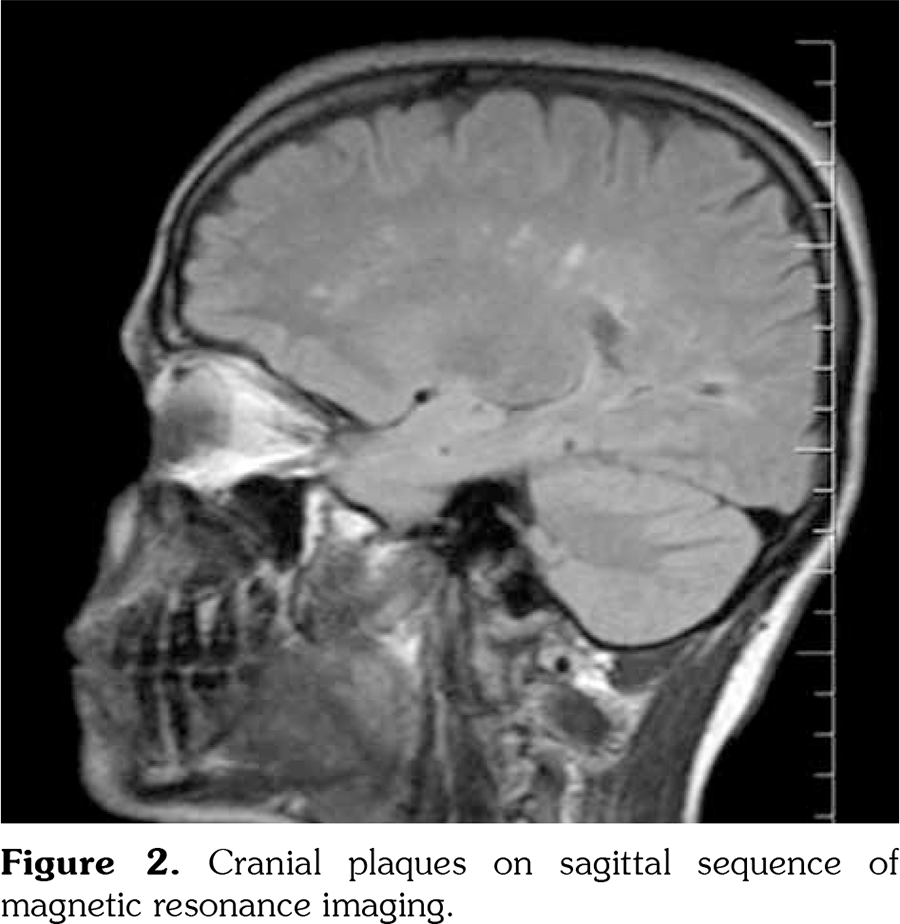

Cranial and spinal magnetic resonance imaging (MRI) showed multiple demyelinating plaques. Thoracal and cranial plaques were not enhancing with contrast agent. Spinal plaques were at the level of T8-T10 and T11 (Figures 1 and 2). Oligoclonal immunoglobulin (Ig) G bands (type II) were detected by immunofixation electrophoresis in cerebrospinal fluid (CSF). Neuromyelitis optica IgG was not found in CSF. Right tibial sensorial evoked potential latency was 64.2 milliseconds and left tibial potential latency was 46.1 milliseconds. He was diagnosed as MS and treated with 1000 mg/daily corticosteroid therapy for seven consecutive days. His hypoesthesia was completely resolved while paraparesis was almost resolved. However, his gait was still ataxic. Interferon (IFN) beta-1a was initiated three times/weekly subcutaneously. On monthly follow-ups, there was no attack for MS. The patient discontinued colchicine treatment by his own will after five months of IFN treatment because he did not suffer from any FMF attacks. He did not suffer even a mild FMF attack from september 2017 until now. He is also under control for MS.